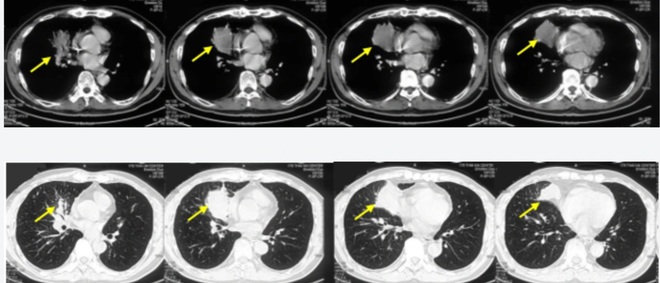

Hình ảnh chụp cắt lớp vi tính lồng ngực khối u thùy dưới phổi phải kích thước 6,1 x 4,8 cm (mũi tên).

Đáng chú ý ở bệnh nhân này, trong thời gian rất ngắn, cách vào viện một tuần, bệnh nhân xuất hiện ho, tức ngực tăng nhiều về đêm. Bệnh nhân tự điều trị thuốc tại nhà nhưng không đỡ nên đi khám.

Tại Bệnh viện Bạch Mai, bệnh nhân được chụp cắt lớp vi tính phát hiện khối u phổi phải, nhập viện điều trị. Trước đó, bệnh nhân có tiền sử hoàn toàn khỏe mạnh.

Kết quả chẩn đoán xác định bệnh nhân ung thư phổi phải di căn xương đa ổ giai đoạn 4, với kết quả mô bệnh học là ung thư biểu mô tuyến, PDL1 (+), đột biến E746_A750 trên exon 19.